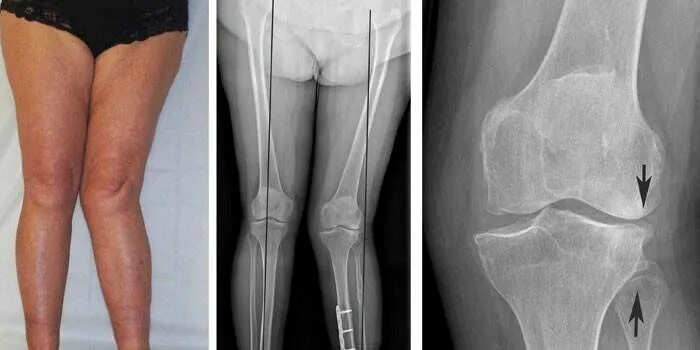

Хобл 1 группа инвалидности. инвалидность 2 группы хобл. хобл группа инвалидности. 2 группа инвалидности при хобл.Инвалидность при артрозе 3 степениГонартроз наколенник коленного. гонартроз 3 степени ортез. бандаж на коленный сустав при артрозе 2 степени.2 группа инвалидности. 3 группа инвалидности. инвалидность группы и степени. 2 группа 3 степень инвалидности.Группы инвалидности по степени трудоспособности. степени инвалидности 3 группы. 2 группа 3 степень инвалидности. инвалидность 1 и 2 степени.Инвалидность при артрозе 3 степениИнвалидность при гонартрозе. нетрудоспособность при остеоартрозе. инвалидизация при артрозе. остеоартроз инвалидность.Коксартроз тазобедренного сустава 2 степени инвалидность. инвалидность 3 степени при коксартрозе тазобедренного. инвалидность при коксартрозе тазобедренного сустава.Инвалидность при артрозе 3 степениГонартроз инвалидность. инвалидизация при артрозе. остеоартроз инвалидность.Коксартроз тазобедренного диагноз. коксартроз тазобедренного сустава инвалидность. коксартроз 2 степени тазобедренного сустава дают ли инвалидность. коксартроз 3 степени тазобедренного сустава инвалидность.Инвалидность при артрозе 3 степениИнвалидность остеоартрит. инвалидизация при артрозе.Инвалидность заболевания. группы инвалидности заболевания. инвалидность по общим болезням. инвалидность заболевания по группам.Инвалидность при артрозе 3 степениГонартроз коленного сустава 2. гонартроз коленного сустава 3. гонартроз 3 степени рентген.1 группа б инвалидности. сетка инвалидности. меланома первая группа инвалидности. инвалидность при трахеостоме.2 группа 3 степень инвалидности. инвалидности 1 2 3 группы пример. категории болезней для инвалидности 1 группы. инвалид 2 группы 3 степени.Инвалидность при гонартрозе. инвалидность при гонартрозе 3 степени.Гипертоническая болезнь 3 риск 4 инвалидность. 3 стадия гипертонии группа инвалидности. гипертоническая болезнь 3 стадии 1 степени риск 4 группа инвалидности. гипертоническая болезнь 2 стадия 2 степени группа риска 3.Группы инвалидности. получение инвалидности. инвалидность группы инвалидности. 2 группа инвалидности это какие заболевания.Коксартроз тазобедренного сустава 3. коксартроз эндопротезирование тазобедренного сустава. диспластический коксартроз тазобедренного сустава. коксартроз тазобедренного сустава 2 степени инвалидность.Инвалидность при артрозе 3 степениМедико-социальную экспертизу для получения инвалидности. мсэ 1 группа инвалидности. медико-социальная экспертиза (мсэ): инвалид, инвалидность. справка об инвалидности ребенка инвалид детства.Коксартроз 2 степени тазобедренного. остеонекроз тазобедренного сустава 2 -3 степени. асептический некроз бедренных костей. коксартроз асептический некроз головки.Инвалидность 2 группы онкология. вторая группа инвалидности по онкологии. 1 группа инвалидности по онкологии. инвалидностью ii группы.2 группа 3 степень инвалидности. инвалидность 2\2 гр. группа инвалидности льготы. 1 группа инвалидности.Инвалидность при артрозе 3 степениАртроз тазобедренного сустава 3 степени положена ли инвалидность. коксартроз 3 степени тазобедренного сустава сняли инвалидность. коксартроз эндопротезирование. коксартроз после эндопротезирования диагноз.Инвалидность при артрозе 3 степениИнвалидность при артрозе 3 степениКоксартроз тазобедренного сустава инвалидность. коксартроз тазобедренного 4 степени инвалидность. инвалидность 3 степени при коксартрозе тазобедренного. коксартроз тазобедренного сустава 2 степени инвалидность.Инвалидность при артрозе 3 степениИнвалидность при артрозе 3 степениМедико-социальная экспертиза (мсэ): инвалид, инвалидность. втэк 3 группа инвалидности. 2 группа инвалидности. мсэ 2 группа инвалидности.Диспластический коксартроз рентген. снимки коксартроза 1.2.3 степени тазобедренного сустава. коксартроз 4 степени тазобедренного. диспластический коксартроз тазобедренного сустава рентген.Инвалидность при артрозе 3 степениИнвалидность при артрозе 3 степениФункциональные классы нарушения функции суставов. степени функциональной недостаточности суставов. степени нарушения функции суставов. функциональное нарушение суставов классификация.Группы инвалидности. вторая группа инвалидности. легкая группа инвалидности. дают ли инвалидность.Получение группы инвалидности. инвалидность по группам. заболевания по инвалидности. сроки получения инвалидности.Инвалидность при артрозе 3 степениИнвалидность при артрозе 3 степениИнвалидность при артрозе 3 степениИнвалидность при артрозе 3 степениСтенокардия формулировка диагноза. инвалидность при ибс. инвалидность заболевания по группам. группа инвалидности при стенокардии.Справка об инвалидности. мсэ и инвалидность по зрению. 2 группа инвалидности. 3 группа инвалидности.Инвалидность при артрозе 3 степениИнвалидность 2 группы онкология. группа инвалидности при болезни. 1 группа инвалидности. группы инвалидности при онкологии группы.Инвалидность при артрозе 3 степениВторая группа инвалидности бессрочно. справка об инвалидности бессрочно. 3 группа инвалидности бессрочно. бессрочная инвалидность 2 группы.Продольное плоскостопие 1. продольно-поперечное плоскостопие 2 степени. продольным или поперечным плоскостопием ii степени. продольное плоскостопие деформация стопы.1 2 3 группа инвалидности. инвалидность группы и степени. степень инвалидности по группам. критерии присвоения группы инвалидности.Первичный гонартроз двусторонний. гонартроз коленного сустава. деформирующий артроз 2. деформирующий артроз 1-2 степени.Инвалидность при артрозе 3 степениПеречень заболеваний для инвалидности. инвалидность 2 группы перечень заболеваний. вторая группа инвалидности болезни. инвалидность 1 и 2 группы перечень заболеваний.Втэк 3 группа инвалидности. форма справки мсэ по инвалидности. мсэк бессрочная инвалидность 2 группы. справка мсэ об инвалидности 1 группы.Справка об инвалидности 3 группы. инвалидность группы инвалидности. вторая группа инвалидности. группа инвалидности бессрочно.Инвалидность при артрозе 3 степениИнвалидность при артрозе 3 степениСтепень инвалидности при остеохондрозе. инвалидность при 3 степени остеохондроза. полагается ли группа инвалидности при заболеваниях позвоночника?. инвалидность по сколиозу 3.Группы инвалидности. третья группа инвалидности. инвалидность по группам. вторая группа инвалидности.Дают ли при инфаркте 3 группу инвалидности. инфаркт миокарда инвалидность. положена ли инвалидность после инфаркта миокарда и стентирования. инвалидность по инфаркту миокарда.Группы инвалидности. степени инвалидности. инвалидность группы и степени. 1 группа инвалидности.Инвалидность при артрозе 3 степениИнвалидность при артрозе 3 степениИнвалидность при артрозе 3 степениИнвалидность при переломе бедра. отсутствие конечности группа инвалидности. группа инвалидности при ампутации голени. группы инвалидности ампутация.Инвалидность группы инвалидности. группа инвалидности при болезни. диагнозы инвалидов. f70 диагноз инвалидность.Инвалидность при артрозе 3 степени